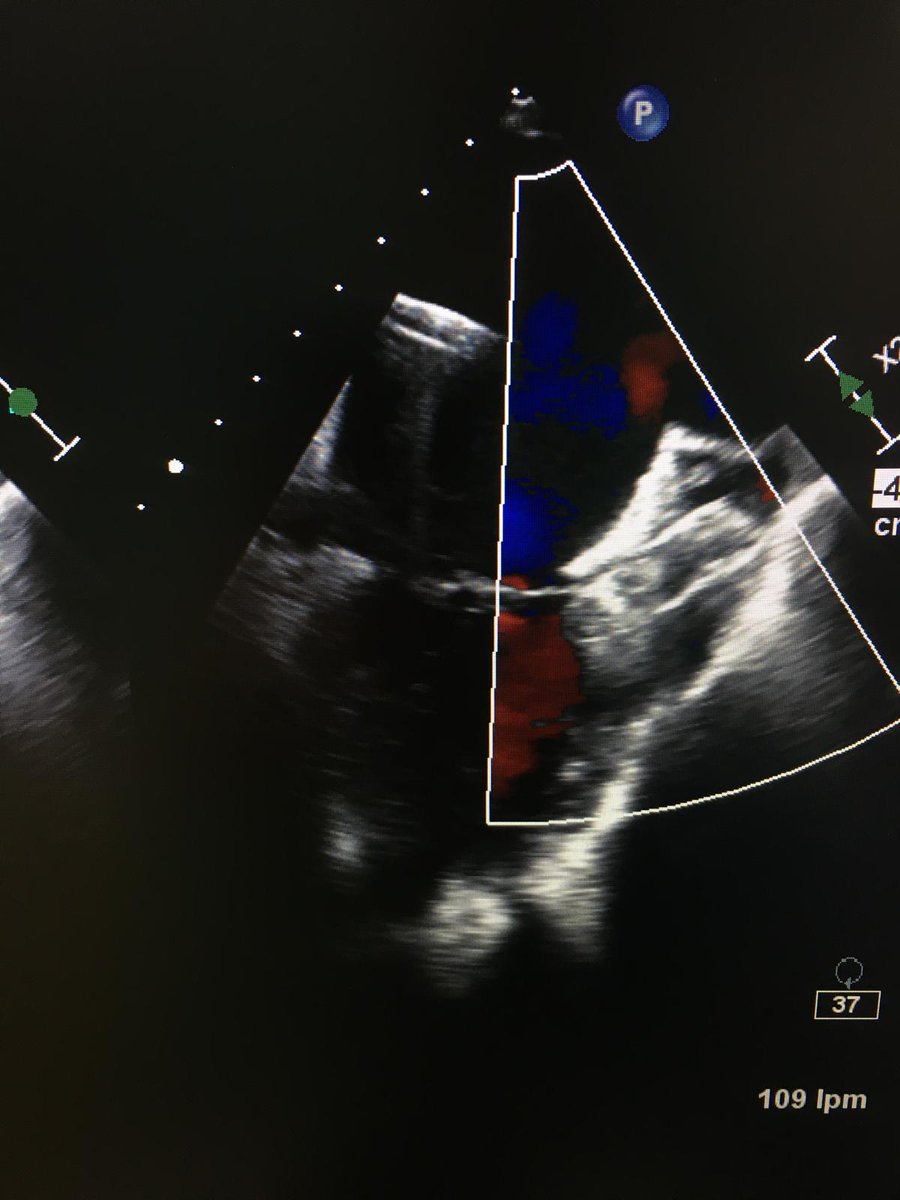

Ambas válvulas (mitral y tricúspide) presentan velos finos, con buena apertura y sin insuficiencia significativa. Aurícula derecha dilatada. Se observa la aorta como único vaso que sale del ventrículo izquierdo/único, con buena apertura e insuficiencia ligera.